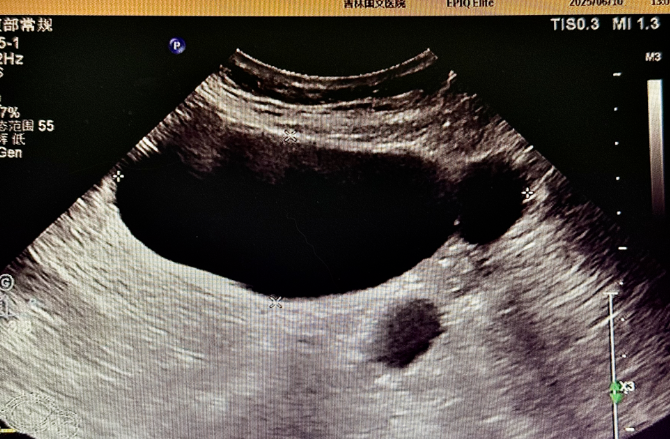

為精準(zhǔn)判斷病情,患者術(shù)前接受了多項影像學(xué)檢查:盆腔 MR 平掃顯示,腹腔內(nèi)存在囊性病灶,周圍伴有管狀影像,為病變定位提供了重要線索,下腹部 CT 進(jìn)一步提示輸卵管擴(kuò)張,腹盆腔內(nèi)可見低密度病灶,與 MR 結(jié)果相互印證,超聲檢查發(fā)現(xiàn)附件區(qū)有管狀無回聲結(jié)構(gòu),經(jīng)超聲科與婦科專家聯(lián)合會診,綜合分析后診斷為輸卵管積水。多項檢查數(shù)據(jù)的交叉驗證,如同為醫(yī)生裝上 “透視眼”,讓隱藏的病灶無所遁形,為后續(xù)手術(shù)方案的制定打下了堅實基礎(chǔ)。